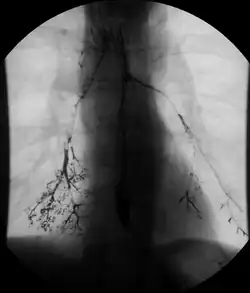

- Enteroclysis, also called small bowel enema, is a barium X-ray examination used to display individual loops of the small intestine by intubating the jejunum and administering barium sulfate followed by methylcellulose or air.[5]

In addition to fasting for 8 hours prior to examination, a laxative may also be necessary for bowel preparation and cleansing.[12] The main aim of this study is to distend the proximal bowel through infusion of large amount of barium suspension. Otherwise, the distension of distal small bowel is generally similar with small bowel follow-through. Therefore, there is a need to pass a tube through the nose into the jejunum (nasojejunal tube) to administer large amount of contrast. This can be unpleasant to the subject, requires more staff, longer procedural time, and higher radiation dose when compared to small bowel follow-through. The indications for enteroclysis are generally similar to small bowel follow-through. Barium suspensions such as diluted E-Z Paque 70% and Baritop 100% can be used. After that, 600 ml of 0.5% methylcellulose is administered after 500 ml of 70% barium suspension is given. Bilbao-Dotter tube and Silk tube can be used to administer barium suspension. The subject should be fasted overnight, any antispasmodic drugs should be stopped one day before the examination, and Tetracaine lozenges can be used 30 minutes before the procedure to numb the throat for nasojejunal tube insertion.[13]

The filling of the small intestines can be viewed continuously using fluoroscopy, or viewed as standard radiographs taken at frequent intervals. The technique is a double-contrast procedure that allows detailed imaging of the entire small intestine. However, the procedure may take 6 hours or longer to complete and is quite uncomfortable to undergo.[23]